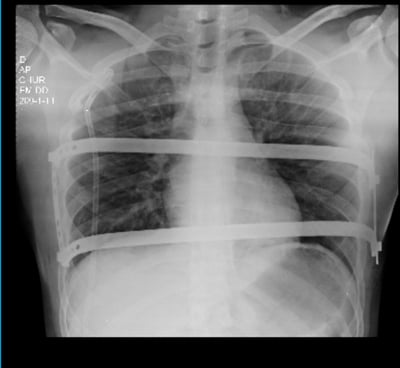

Veja casos de antes e depois